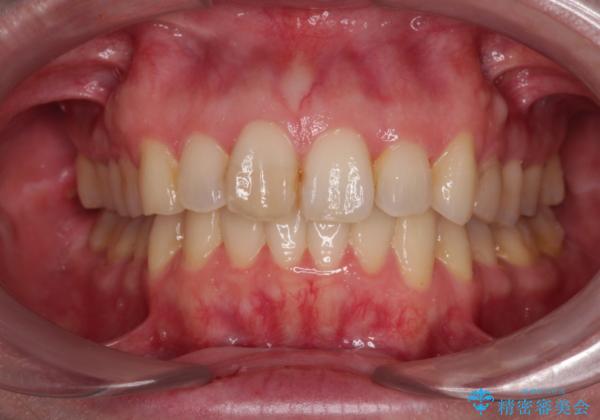

カリエール・ディスタライザーを併用したインビザライン矯正治療

- 上顎前歯の突出感と、前歯のクロスバイトを気にして来院された患者様です。

前歯の叢生と口元の閉じにくさを気にして来院された患者様です。

奥歯の咬み合わせを見ると、上顎が下顎に対して相対的に前方にありました。

口元の閉じにくさを改善するためには、上顎臼歯を後方に移動させた咬み合わせにする必要があります。

インビザライン単体で改善することも可能ですが、達成する可能性が高くないため、カリエールディスタライザーという補助装置を併用して、より確実性を上げることとしました。

奥歯の咬み合わせを改善しながら、並行してインビザラインで歯列を整えることとしました。

カリエール・ディスタライザーを用いたことで上顎前歯の突出感はスムーズに解消され、歯列不正は1年半ほどでほぼ改善することができました。

しかし、その後インビザライン特有の奥歯がうまく噛めないという問題が長引き、改善に1年近い期間を要することとなりました。